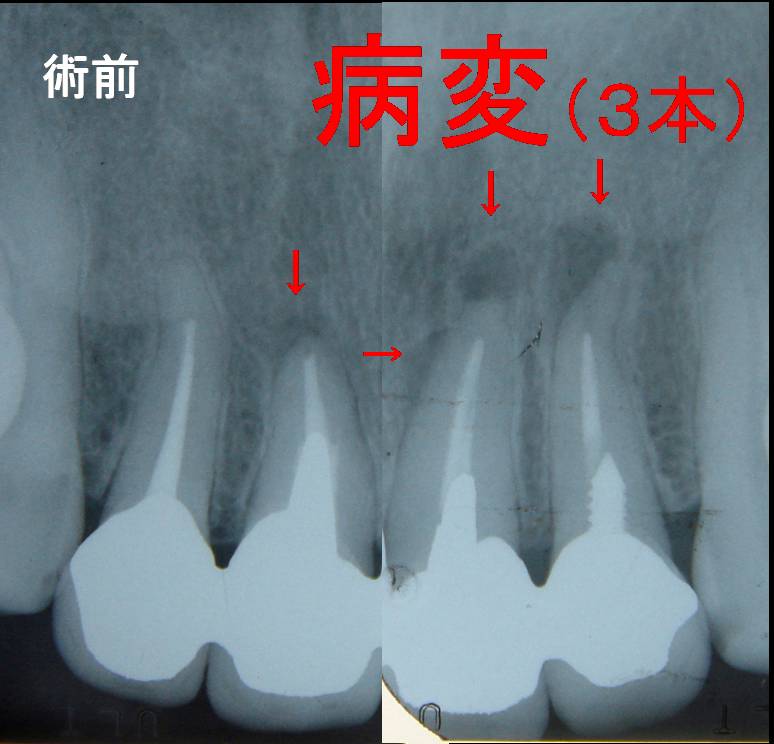

術前

3本の根尖病変

初診時

術前レントゲン:http://www.eedental.jp/blog/archives/2009_5_9_431.html

左上2

左上1

右上1

の3本に「病変」所見がありました。

赤丸で囲んである黒い部分ここに病変があり

この黒く見える場所の骨は溶けており空洞化しています。

(レントゲンで見える場所:骨の中に小さな風船(膿の袋)があると思ってください^^;)